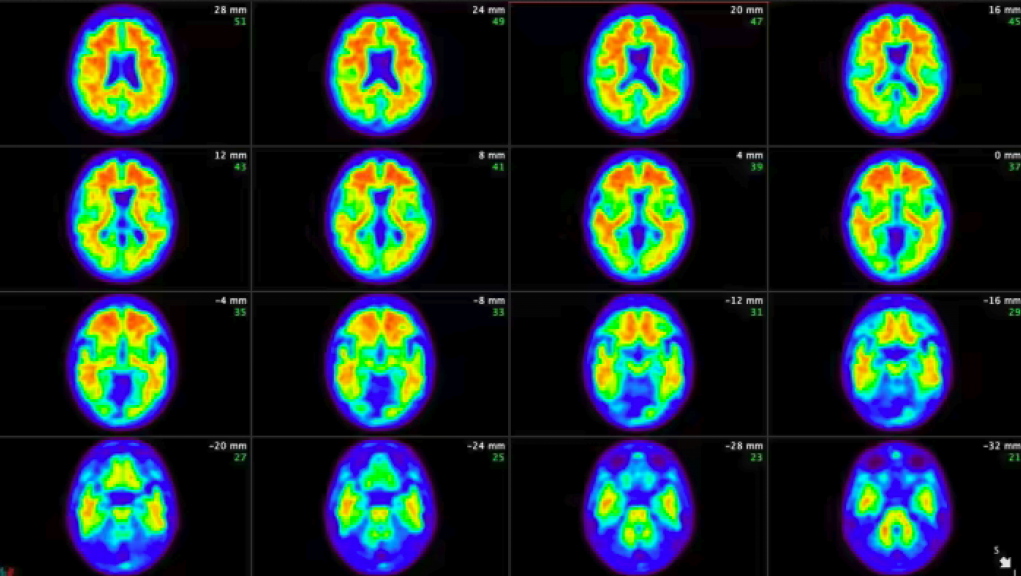

Both lecanemab and donanemab are based on antibodies against amyloid, one of the toxic proteins that build up in the brain as Alzheimer’s proceeds, but they worked at different stages of the process, Oakley said.

Lecanemab targets amyloid as it begins to form fibers in the brain while donanemab is active at a later stage, when the fibers have clumped together into larger accumulations of plaque. The main adverse side effect of both drugs was swelling and bleeding of the brain in a small minority of patients.

It cleared amyloid plaques completely from the brain in some participants, who were then taken off the drug.